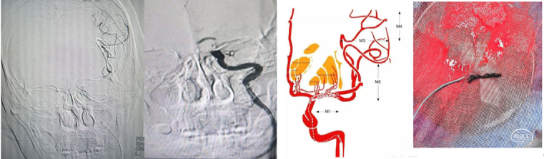

1、 同时存在颈内动脉起始部狭窄或闭塞,远端大脑中动脉血栓。下图1

1、90cm 6F 长鞘+单弯导管+0.35泥鳅(或加硬)导丝建立通路,导丝于颈外动脉内走远起到牵拉作用,配合单弯导管将长鞘置于颈总动脉。下图2

2、035in泥鳅导丝(或加硬泥鳅导丝)携5F 单弯导管+6F 中间导管突破近端闭塞段,并将6F中间导管走远,随后在充分同轴下(像竹笋一样 )将6F长鞘越过近端闭塞段,起到较大阻断血流的作用。下图3、4

常常使用的近端球囊阻断技术包括球囊Guiding或MoMa技术的运用,在此基础上,联合远端滤过保护装置可进一步降低血栓逃逸的机率,但由于增加了操作步骤和手术难度,不可避免也增加了手术风险。相关操作示意见下图。

球囊Guiding或MoMa技术近端阻断联合/不联合远端滤过保护装置(引自高峰—“峰回路转”)

a.远端滤过保护装置;b.近端球囊Guiding联合远端滤过保护装置;c.近端阻断型保护装置(MoMa技术);d.近端阻断型(MoMa技术)联合远端滤过保护装置。

步骤一:释放Syphonet®取栓支架远端保护

(1) 微导丝、微导管突破闭塞段后下图1;

(2)将Syphonet®取栓支架跨越M段与颈内动脉末端释放,起到颅内远端血管的保护作用。下图2

利用盲交换技术将微导管撤出体外,通过指引导管足量、足压力造影初步鉴别闭塞段病变性质。下图3

沿Syphonet®取栓支架输送导丝送入小直径的球囊扩张导管(2mm-2.5mm),由远及近依次对可疑病变部位进行扩张,后再次足量、足压力造影,明确闭塞段内原始病变部位、继发血栓部位和假性闭塞部位。下图1、2